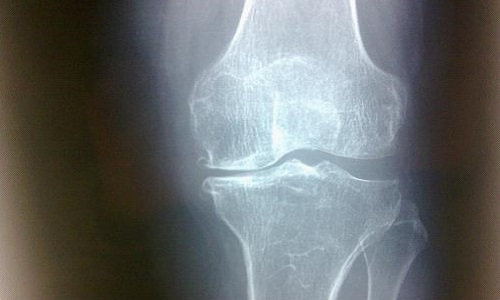

约半数患者出现关节疼痛肿胀、关节积液。以膝踝关节受累多见,尚可累及肘腕、掌指关节和跖趾关节,一般呈不对称性,疼痛以夜间为主,表现为关节轻度酸痛乃至剧烈疼痛。体征包括关节局部发红、发热、触痛肿胀、关节积液和活动受限,也有表现为无痛性关节积液。在没有大量肌肉复盖的部位,由于长骨骨膜新骨形成,可致前臂或小腿日益增粗,腕及踝关节亦相应粗大。

骨改变包括骨膜水肿、炎细胞浸润,随后有骨膜增厚、骨样基质沉着、矿化、新骨形成,骨皮质因与骨膜新生骨连接在一起而增厚。